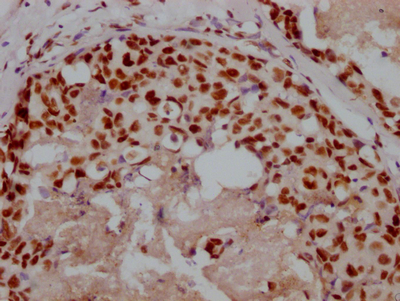

Immunohistochemistry of paraffin-embedded human pancreatic tissue using CSB-PA854079ESR1HU at dilution of 1:100